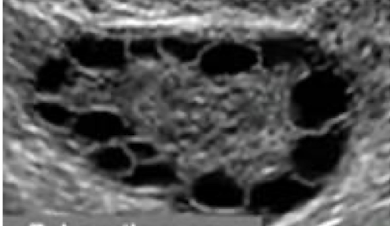

Polycystic ovary

What is this and what type of scan

Ovarian Cyst, Pelvic US